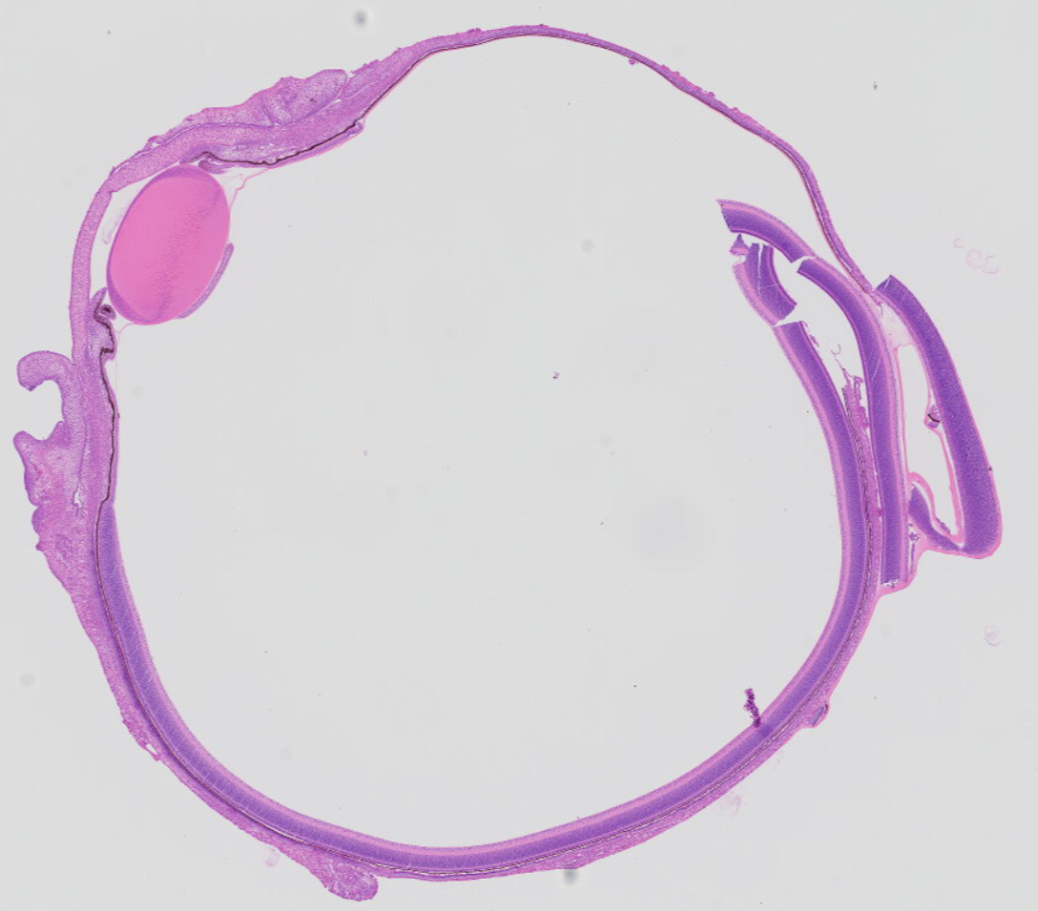

您的位置:首页 >> 产品介绍 >> 鸡眼球HE扫描切片

鸡眼球HE扫描切片

鸡眼球HE图片描述:色素上皮细胞层、感光细胞层、双极细胞层、节细胞层,各层细胞结构排列整齐,形态良好,未见断裂,细胞间无裂隙,细胞核清晰可见,节细胞层排列整齐紧密,节细胞条带、感光细胞层密度及宽度正常。